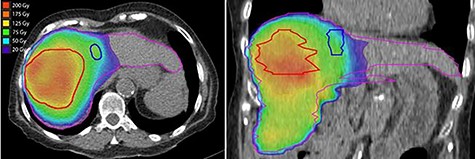

Post-treatment dosimetry done using the Bremsstrahlung liver SPECT image and the Sure Plan software demonstrated that the mean dose delivered to the main right liver lobe tumor (GTV) was 156 Gy. Ninety-five percent of the GTV received 108 Gy with a max dose of 213 Gy. The mean dose to the Segment IVA lesion was only 62 Gy, with 95% of the lesion receiving 36 Gy (Figs 8 and 9).

Dose–volume histogram of the main lesion (GTV) localized in the right liver lobe (red), the dose to the Segment IVA lesion (blue) and the dose to the left liver lobe (yellow).

Axial and coronal views of the Y-90 dose distribution; the majority of the uptake is within the GTV with minor uptake in the Segment IVA lesion.

In this case report, we demonstrate that the post-Y-90 TARE dosimetry was predictive of treatment response. The main tumor which received a mean dose of 156 Gy showed a complete pathologic response, while the satellite nodule that was treated to a mean dose of 62 Gy showed only a partial response.

Since this was a procedure performed in preparation for a right lobectomy, a mean dose to the right liver lobe of 74 Gy was deemed acceptable. The left liver lobe was almost totally spared from any radiation with a mean dose of 25 Gy and 95% of the lobe receiving 3.5 Gy. These findings are in agreement with other published data indicating that delivering a dose higher that 100 Gy during Y-90 TARE leads to good tumor control [2]. The benefit of using Y-90 TARE to deliver an ablative radiation dose is that this treatment technique completely spares the surrounding extra hepatic organs from radiation. The use of dosimetry software brings important data for outcome analysis.